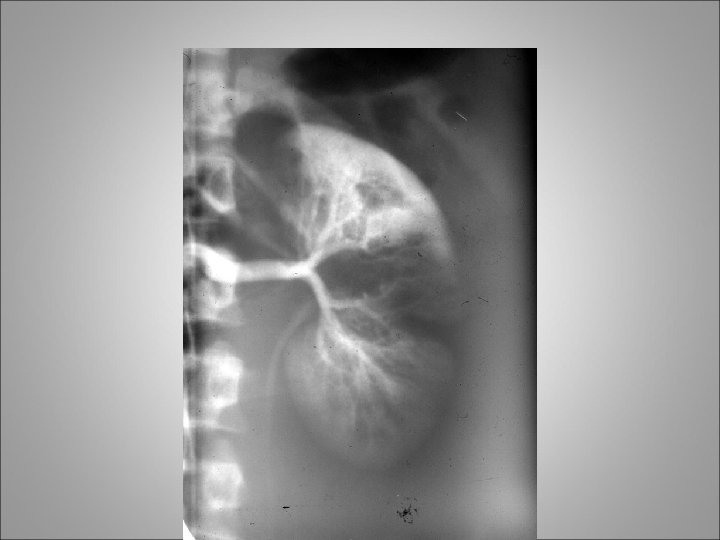

Delayed imaging Injury to collecting system with extravasation

Delayed imaging Renal pelvis injury with leak of urine